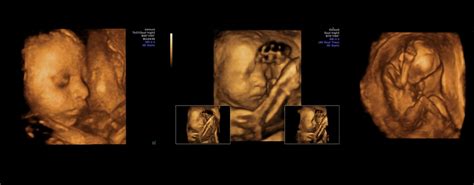

- Ecografie Detaliată: Ecografia detaliată permite evaluarea feților pentru posibile anomalii structurale. Gravidei i se vor recomanda efectuarea unor analize în timpul sarcinii, ecografii de sarcină mai dese și teste pentru identificarea unor eventuale boli congenitale. Astfel, pot fi indicate teste non-stres, profiluri biofizice, teste de stres la contracție și ecografii Doppler, pentru a evalua fluxul sanguin în cordonul ombilical.